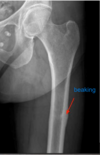

a patient presents with prodromal pain and localized periosteal or cortical thickening of the cortex that looks like "beaking". Dx?

atypical femoral fracture d/t bisphosphonates